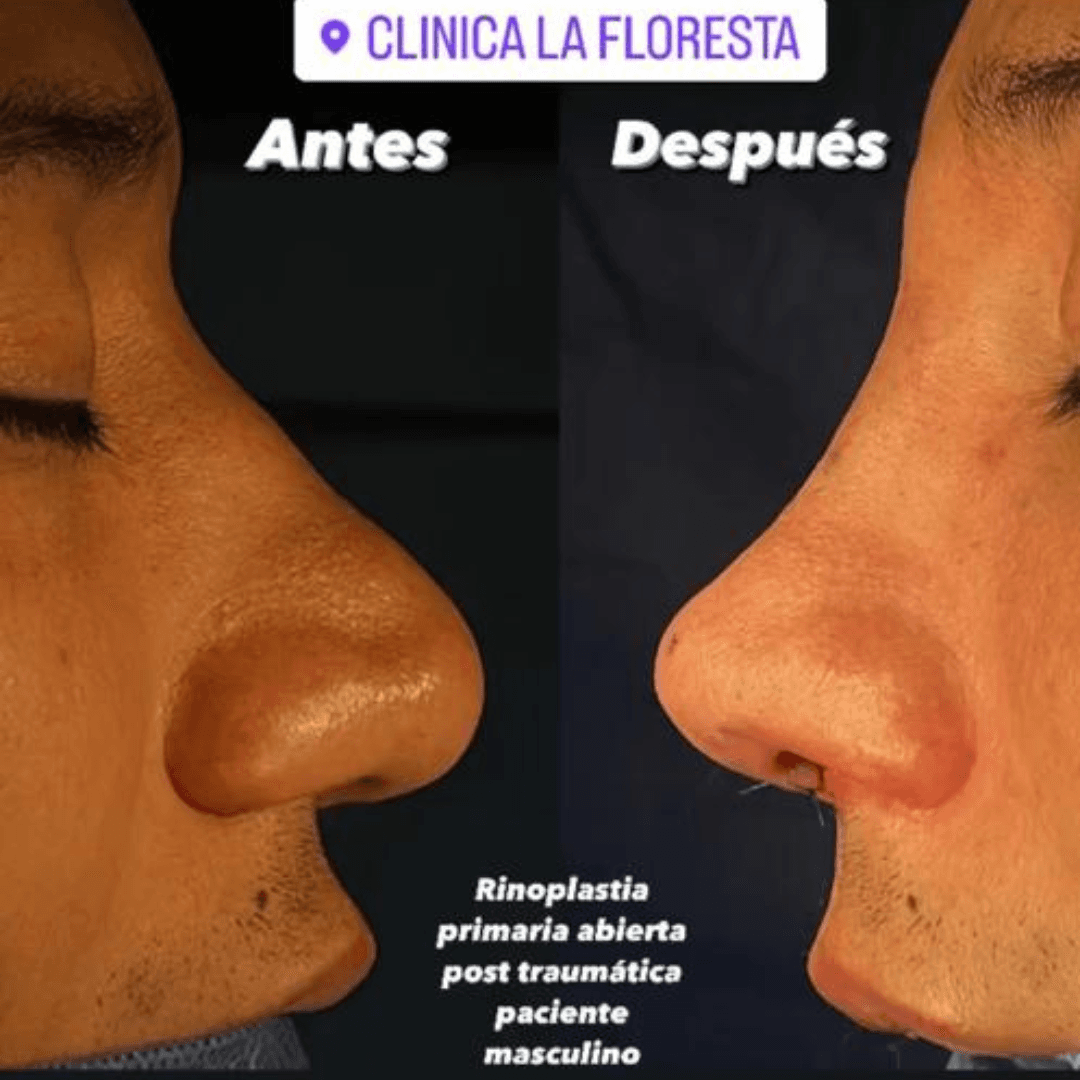

Rinoplastia ultrasonica